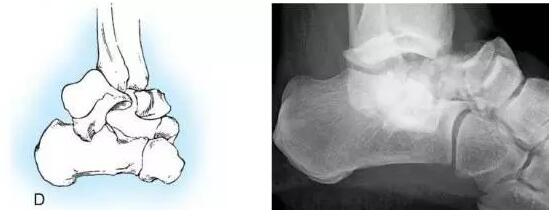

HawkinsⅣ型:距骨颈骨折移位伴距舟关节胫距 关节和距下关节脱位或半脱位